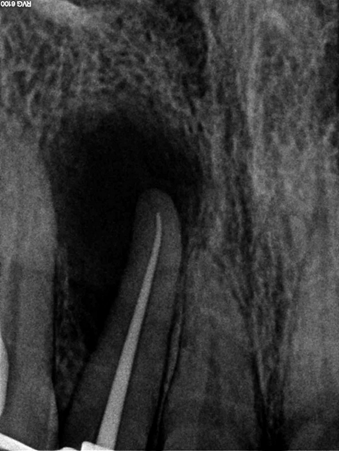

- Проходим корневые каналы специальным инструментом и расширяем их до круглого сечения. При этом применяется ЭДТА для частичной деминерализации и облегчения прохождения.

- Промываем каналы горячим раствором гипохлорита натрия. Это который «Белизна», только чистый, каталитического происхождения и другой концентрации. Стоматолог в каждый канал специальным ирригатором вводит тёплый раствор, который убивает любую органику, затекает в микрощели и ответвления. В определённых техниках это может сочетаться с ультразвуком как в УЗ-ваннах для отмывки плат и ювелирных изделий.

- Остатки гипохлорита вымываем стерильным физраствором и хлоргексидином высокой концентрации. В идеале на этом этапе мы должны убрать весь детрит, опилки и остатки погибших в хлорке бактерий на всём протяжении канала.

- Закладываем лечебную пасту на базе гидроксида кальция. Это щёлочь, которая очень быстро убьёт всех оставшихся бактерий, пропитает дентин и частично выйдет за пределы верхушки корня. За счёт щелочной среды и избытка ионов кальция произойдёт стимуляция остеобластов, которые начнут выращивать кость на месте дефекта, созданного кистой. Лечебная паста обычно остаётся на 14 дней.

- Через 14 дней ещё раз промываем всё гипохлоритом и хлоргексидином, после чего пломбируем канал, стараясь заполнить все боковые ответвления.